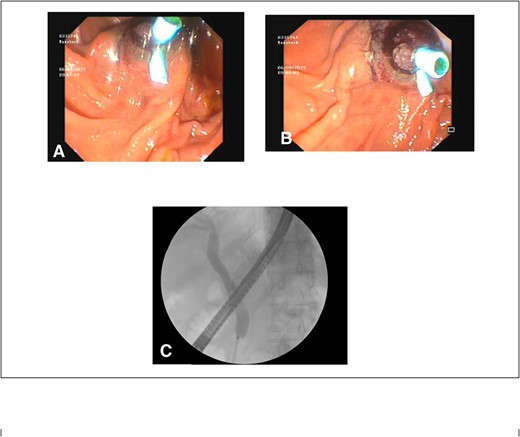

After consultation with our Hepatobiliary service, the consensus was for the patient to undergo an urgent ERCP. Intraoperatively, a duodenoscope was introduced through the mouth and was advanced to the duodenum at the ampulla of Vater. The major papillae were bulging and a malignant appearing infiltrative mass was visualized. A tapered tip cannula was inserted through the ampulla and contrast was injected, revealing a patent PD and a single 18-mm long stenosis of the distal third of the CBD with significant dilatation of the proximal CBD and intrahepatic ducts (Fig. 2). A 10Fr 7-cm transpapillary plastic stent was inserted with a single internal flap, 5.5 cm, into the CBD. The biliary pancreatic junction was biopsied with cold forceps for histology. Cholangiopancreatography revealed the stent was in good position with good flow of contrast into the duodenum beyond the filling defect (Fig. 3).

(A) and (B) endoscopic images showing a single plastic stent inserted into the distal CBD, protruding into the second part of the duodenum; (C) position confirmed on cholangiopancreatography revealing resolution of distal CBD filling defect.